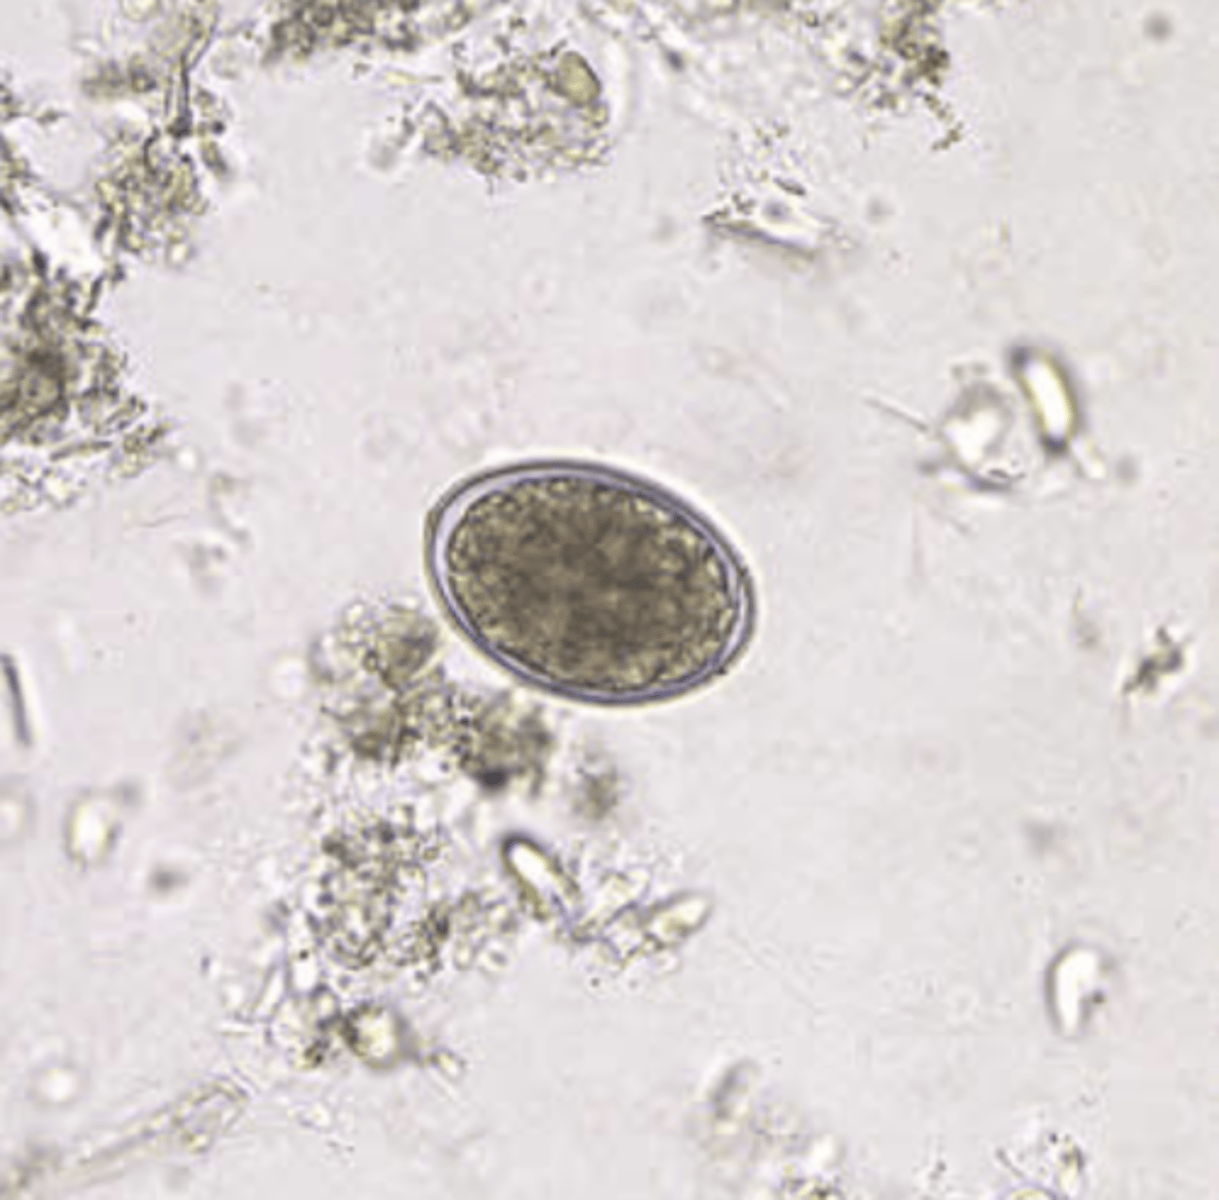

Hookworm